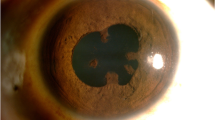

Among 100 eyes of 100 patients, PCR analysis confirmed the initial clinical diagnosis in 70.1% patients. The correlation of pre- and post-PCR diagnoses is depicted in Table 2. But PCR altered our treatment in 17.7%. The overall sensitivity and specificity of PCR analysis of ocular fluid was found to be 90.2 and 93.9%, respectively. The PPV, defined as the likelihood of having disease related to the tested infectious agent given positive PCR results, was 93.9% and NPV, defined as the likelihood of not having the specified disease given negative PCR results, was 90.2% in the overall analysis (Table 3). The sensitivity, specificity, and predictive values of the individual organism were also analyzed (Table 4) and the agarose gel electrophotogram of detection of various DNA genomes shown in Figs. 1, 2, 3, and 4. Real-time PCR was done for M. tuberculosis and this showed the quantitative value ranging from 32 to 2722 c/ml.